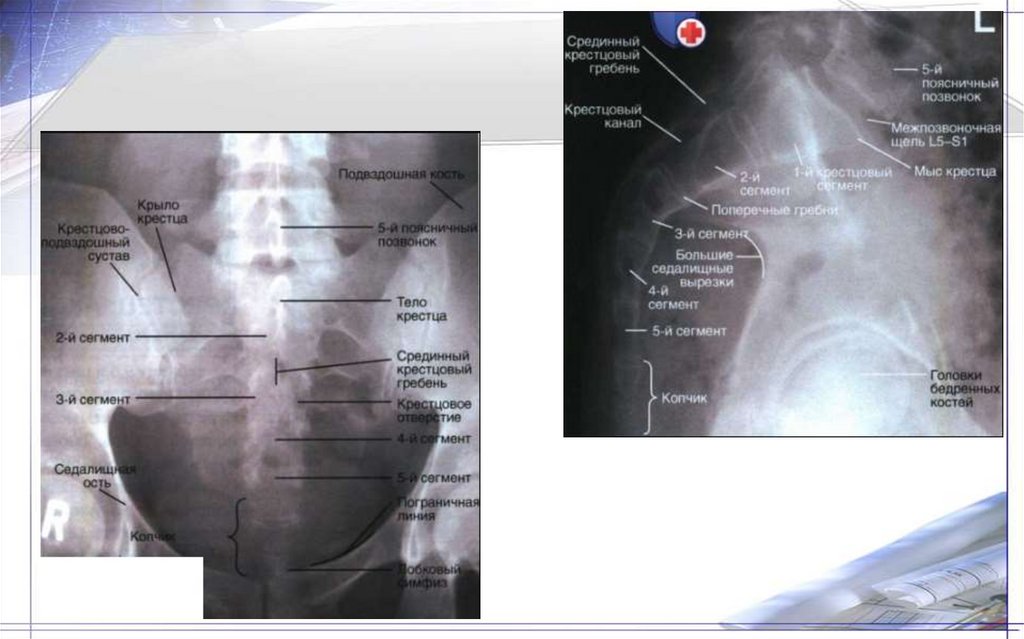

27. Крестец (os sacrum) и копчик (os coccygis)